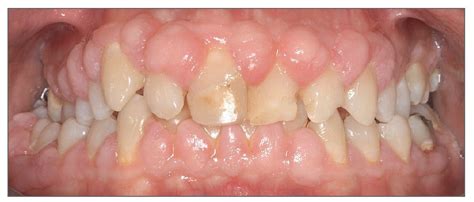

Aumento gingival inducido por placa/fármacos

En esta condición el problema radica en que los tejidos gingivales son hiperplásicos y cubren las coronas clínicas, lo que da lugar a un aspecto poco estético. La mayoría de las veces esta condición está relacionada con la presencia de placa dental y de inflamación pero también puede verse asociada a medicaciones como la fenitoína, la ciclosporina y bloqueantes de los canales del calcio. El tratamiento de estos casos debe enfocarse hacia la higiene oral meticulosa. A veces es necesario recurrir a cirugía periodontal para eliminar la excesiva cantidad de tejidos blandos.

Varón joven con hiperplasia gingival pronunciada debido a un tratamiento con ciclosporina.